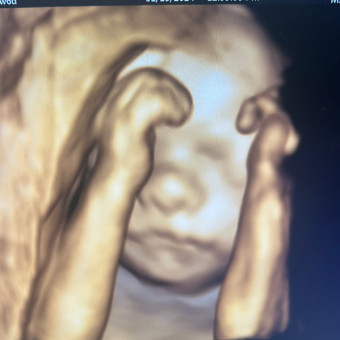

Babylist Registry Photo

Baby Livingstone’s Registry